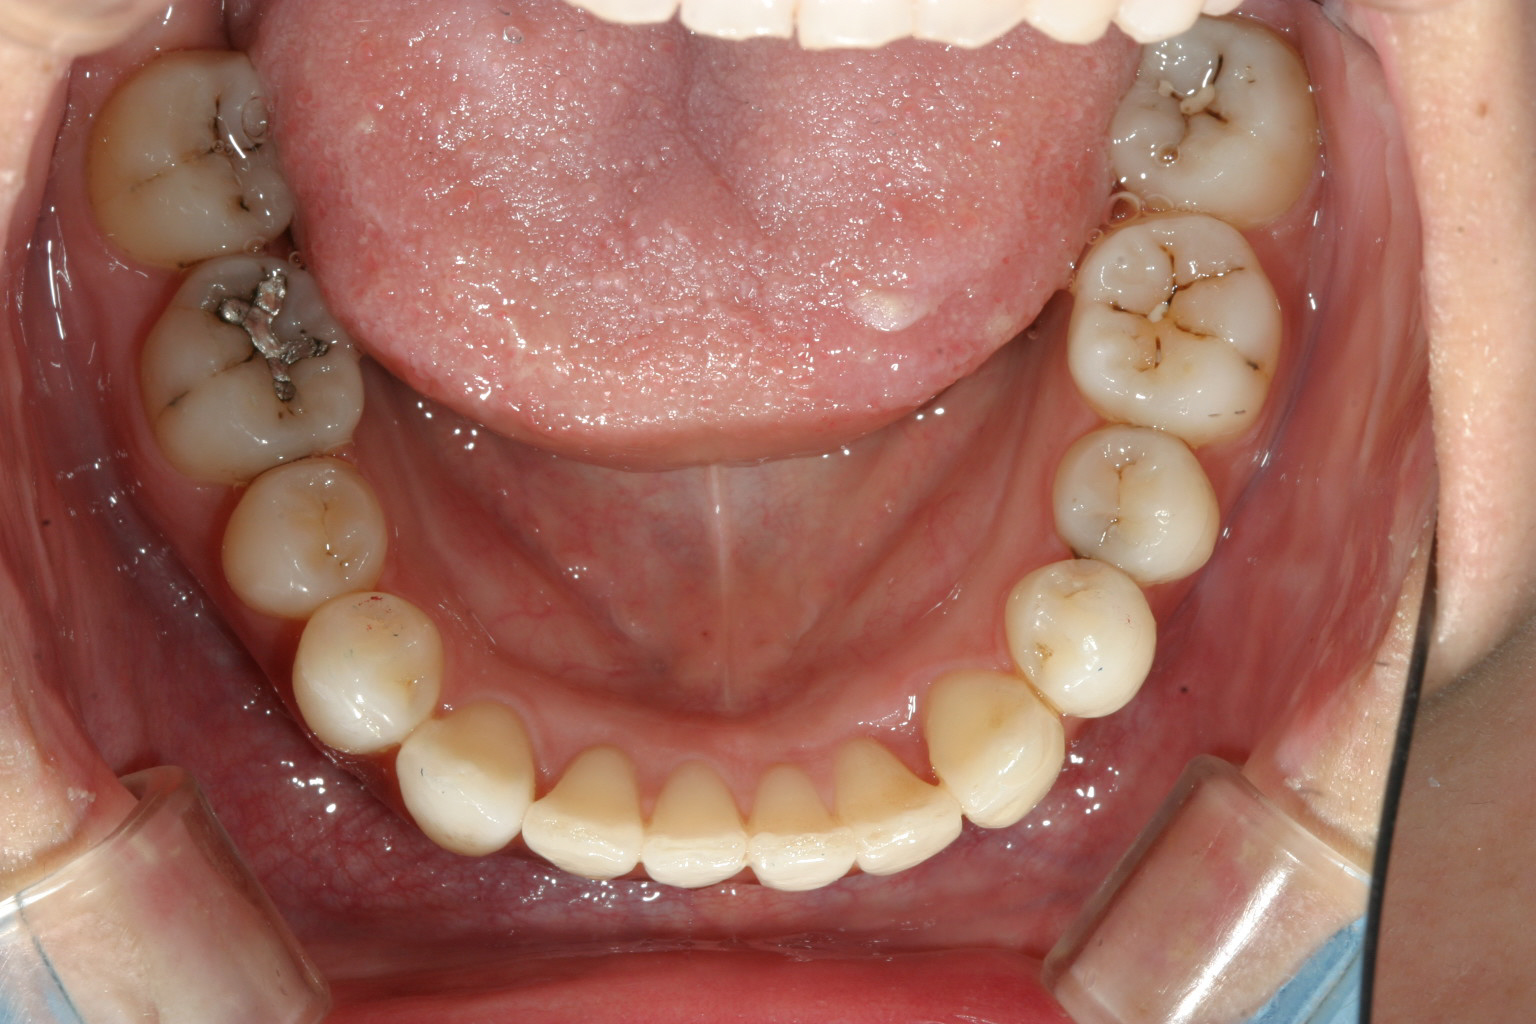

下顎も綺麗ですね~

側面観もいい感じです。